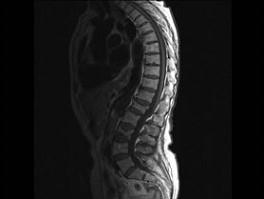

问题 女,85岁,背部疼痛,脊柱后凸1个月余,请结合影像学检查,选出最可能的诊断 ( )

选项 A、化脓性脊柱炎 B、脊椎退行性变 C、脊椎结核 D、脊柱转移瘤 E、椎体骨折

答案 E